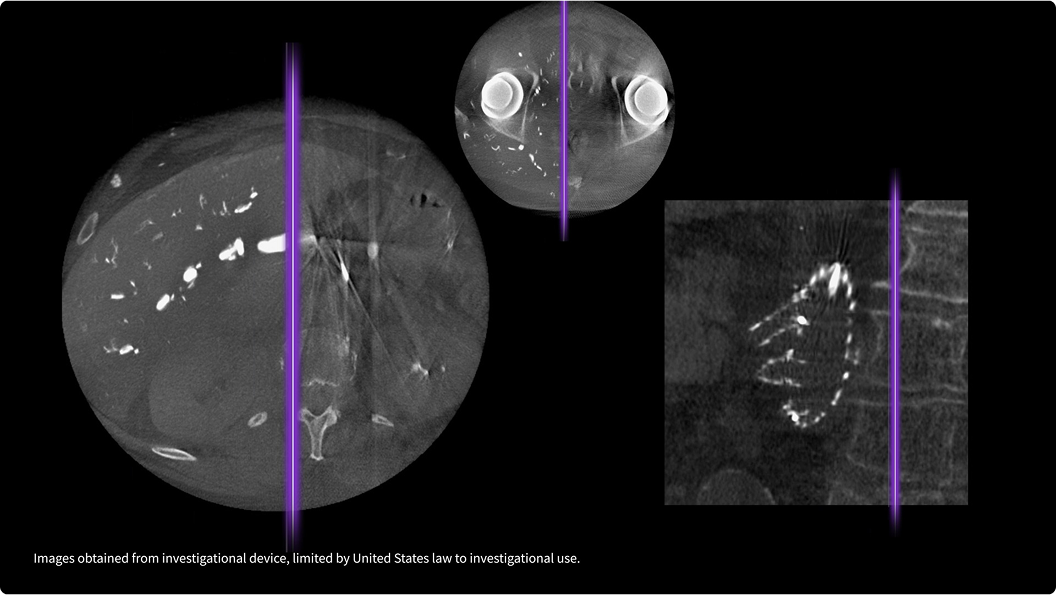

Spine Trace

Welcome to easy 3D in 1/2 the time. Simply trace the spine and the system automatically acquires the volume and displays the coronal view - with 83% less keystrokes.